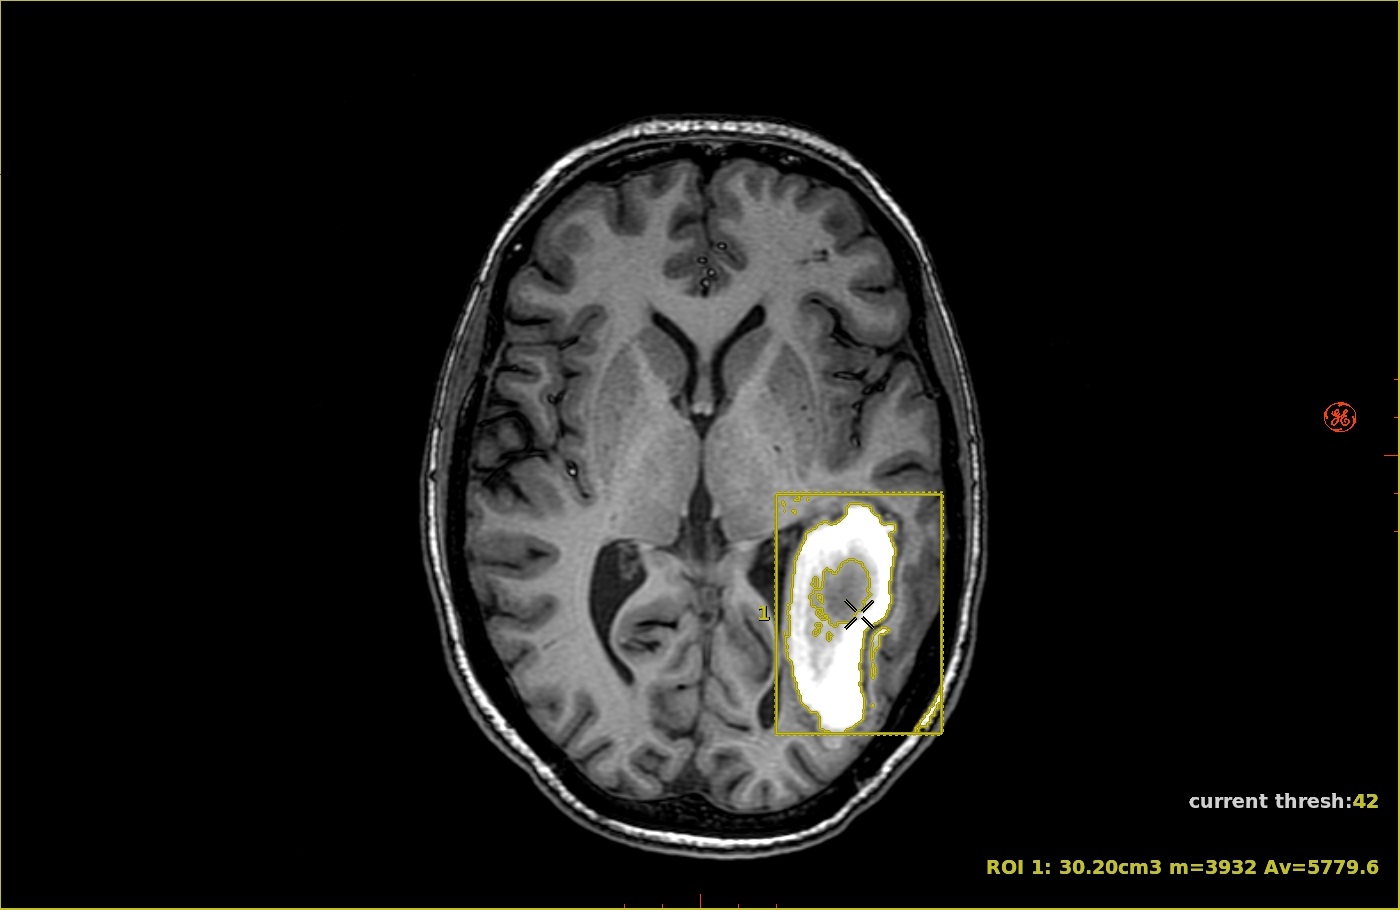

Figure 1. Image with 3D ROI deposited